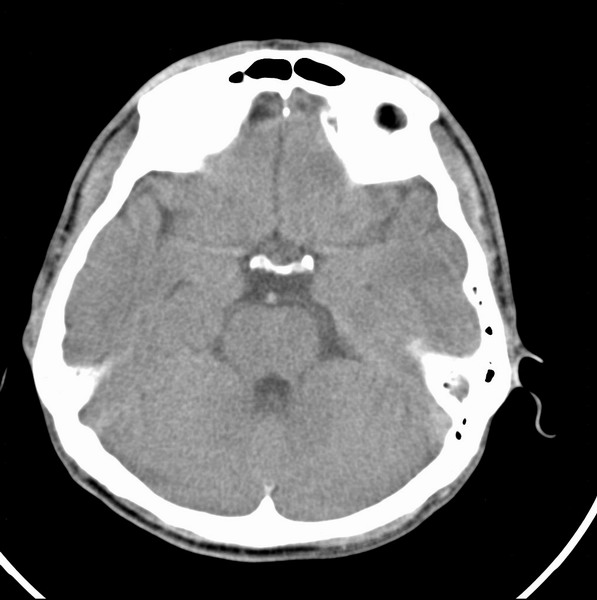

标题: CT21509:额叶低密度影

男、29

突发痴呆,失语,记忆减退,反应迟钝二十小时。

右侧额叶低密度影,边界清晰,无占位效应,符合:额叶皮质脑软化灶。

双额叶脑沟增深增宽,皮质性脑萎缩可以考虑么?

左额叶也有类圆形低密度影,同右侧低密度灶近颅底一层同层,病灶周脑实质密度似稍高,成环状,这个没有问题么?

考虑右侧额叶脑软化灶;建议必要时行mri检查排除其他。

考虑皮质软化灶。不考虑胶质瘤,是因为胶质瘤一般发生于白质内。